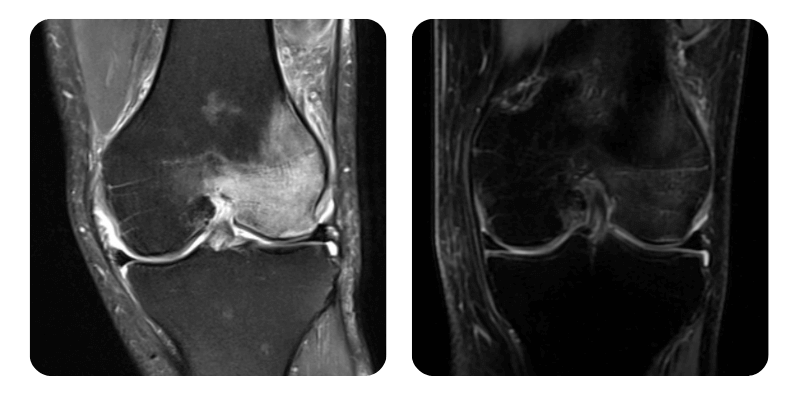

Prima

Dopo

V.I., 58 anni - Necrosi asettica del condilo femorale interno sinistro

Evoluzione: Il paziente torna a controllo dopo 20 sedute e riferisce riduzione del dolore a 1/10 (da 6-7/10), con lieve fastidio solo in alcuni movimenti. Radiologicamente si osserva riduzione dell edema di circa l 80% e significativo miglioramento clinico.